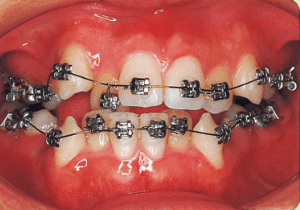

16 Before surgery 7-21-’98 17 years

17 After surgery 8-11-’98 17 years 1 month

Although early treatment improved the slight deviation observed during the deciduous dentition stage, it became apparent that the deviation increased with age, eventually exceeding the limits of treatment. This appears to be an innate deviation, and the developmental pattern observed in this case seems to disregard the occlusion. Four first premolars were extracted (15), crowding was corrected and space closure was performed (16), and surgical intervention improved the deviation (17).